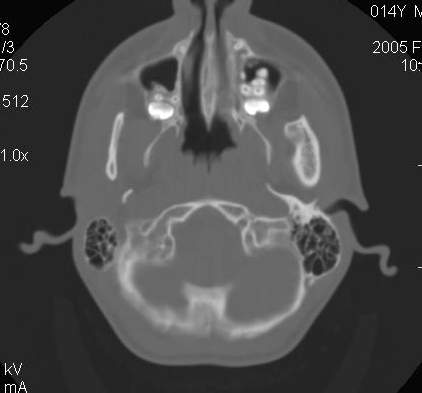

Пациент В., 13 лет. Диагноз: Костный анкилоз левого височно-нижнечелюстного сустава (ВНЧС), левосторонняя микрогения. Болеет с 2-х летнего возраста. Возможная причина развития анкилоза – воспалительный процесс (в первые 1,5 года жизни часто болел простудными заболеваниями, травму родители отрицают). В 3 и 5 лет проводилась редрессация – безуспешно. Прилагаются: ортопантомограмма, кадры СКТ с 3Д реконструкцией. Вопросы: определение тактики лечения – вид и сроки реконструктивно-пластической операции (этапов операции), а именно – неоартропластики и устранения микрогении, медикаментозная терапия в до- и послеоперационный период, ортодонтическое лечение.